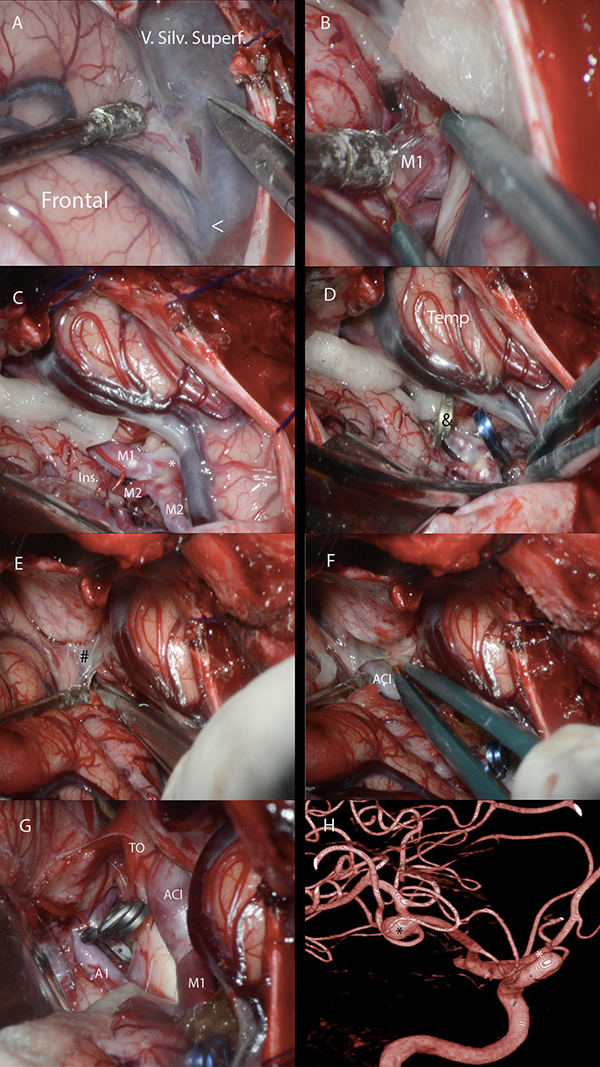

Figura 10: A-G. Fotos quirúrgicas de disección de la FS para clipado de aneurismas de bifurcación de ACM derecha y de arteria comunicante anterior. La disección comienza 10-15 mm proximal a la confluencia venosa silviana. El límite medial de la cisterna silviana es la membrana silviana proximal que se adhiere superiormente a la estría olfatoria lateral e, inferiormente, a la incisura rinal. Su apertura permite el acceso a la cisterna carotídea. V. Silv. Superf: vena silviana superficial; Ins: ínsula; Temp: lóbulo temporal; TO: tracto óptico; ACI: arteria carótida interna; <: confluencia venosa silviana; *: aneurisma; &: clip transitorio; #: membrana silviana proximal. H. Angiografía digital carótida derecha correspondiente. *: aneurisma.

Durante la cirugía, con la membrana aracnoidea intacta, no es fácil identificar las estructuras anatómicas como se hace en los especímenes cadavéricos disecados. Es por esto que los cirujanos pueden usar como punto de referencia para localizar al punto silviano anterior al área más prominente y anterior del giro frontal inferior que se continúa, luego de un borde agudo, con la superficie basal del cerebro. Esta área prominente es la pars orbitalis (Figura 9A). Los giros frontoorbitarios y la superficie basal de la FS solamente son expuestos luego de que el ala menor del esfenoides es removida. Unos pocos milímetros posteriores a esta área, uno puede asumir con seguridad que se localiza la pars triangularis. Más aún, la punta de la pars triangularis suele apuntar a un ensanchamiento prominente de la FS: el punto silviano anterior (Figura 3). También, dado que el punto silviano anterior se localiza donde la fisura silviana pasa de la superficie basal a la lateral, ubicar el sitio donde la fisura cambia de sentido, es otra forma de encontrar este punto microquirúrgico. Finalmente, cuando la parte superficial de la FS está deformada porque el opérculo frontal indenta al temporal, o viceversa, o, cuando la membrana aracnoidea es particularmente opaca, el neurocirujano debe localizar la unión de la vena superficial temporal con la frontal. Este punto es nombrado en la literatura como “confluencia venosa silviana”. El punto silviano anterior se localiza unos milímetros proximales a la confluencia venosa silviana (Figura 8B y 10A).

Los autores comienzan a disecar la FS en el punto silviano anterior debido a que allí se encuentra una “subcisterna” aracnoidea natural generada por una retracción espontánea de la punta de la pars triangularis (Figura 5A). Además, la orientación oblicua inferior en el plano coronal del plano polar del lóbulo temporal (Figura 11C y D), así como también, su dirección lateromedial, contribuyen a la amplificación del espacio subaracnoideo en este punto microquirúrgico esencial. Para acceder a las cisternas aracnoideas basales, la fisura es disecada desde la superficie lateral a la basal. Solo cuando es necesario, las cisternas carotídeas, interpeduncular y quiasmática son abiertas previamente. Esto es útil, por ejemplo, cuando hay hipertensión intracraneal debido a la ruptura de un aneurisma, y se precisa bajar la tensión para realizar la disección. Debe ser tenido en cuenta que para liberar una cantidad considerable de líquido cefalorraquídeo (LCR) con este propósito, es recomendable abrir la cisterna carotídea, así como también la interpeduncular, a través de la disección de la membrana de Liliequist. La cisterna carotídea es una cisterna relativamente pequeña, que, si es abierta aisladamente, solo liberará una pequeña cantidad de LCR.

Con una hoja de bisturí N 11, y retrayendo gentilmente el opérculo con una cánula de aspiración delicada con mínima presión de succión, se incide la membrana aracnoidea, preferiblemente en el lado frontal de la vena silviana superficial (Figura 10A). Consecuentemente, de necesitarse retraer el lóbulo frontal con una espátula, las venas serán mejor preservadas. El cirujano debe siempre intentar preservar el drenaje venoso. Sin embargo, solo si es imperativo las venas silvianas pueden ser coaguladas. No se debe usar sistemáticamente retractores estáticos. El uso de pequeños algodones permite una suave separación de las estructuras cerebrales con mínima presión (Figura 10B). Más aún, cuanto más se expone al lóbulo temporal en la craneotomía, más simple será abrir la fisura. Así también, cuanto más se drilla la pared lateral y techo de la órbita y el ala menor del esfenoides, será necesaria menor retracción cerebral y se conseguirá más exposición de la parte basal. Continuando desde el punto de inicio, las membranas aracnoideas son incididas con una hoja de bisturí o con microtijeras.

El primer compartimiento silviano que es disecado desde el punto silviano anterior es el compartimiento opercular anterior. La mayoría de las FS tienen un compartimiento opercular anterior curvilíneo irregular. Esto se debe frecuentemente a una pars orbitalis prominente que indenta y comprime al plano temporal. Una vez que este compartimiento es disecado, si el cirujano continúa proximalmente y en profundidad por la fisura, se accede al compartimiento esfenoidal. Con una cánula de aspiración delicada con mínima presión de succión, pinzas bipolares bayonetada y microtijeras, se progresa la disección.

Las ramas y segmentos de la ACM no siempre se identifican con claridad. En función de poder hacerlo, es útil disecar los vasos arteriales desde distal a proximal hasta que la bifurcación carotídea es identificada, y luego seguir a la ACM en dirección opuesta, de proximal a distal. M1 debe ser disecada por su cara anterior. Esto es porque las arterias lenticuloestriadas usualmente nacen de su cara superior o posterosuperior (Figura 1C,10C, 10D).

El límite medial de la cisterna silviana es la membrana silviana proximal que tiene un color blanco perlado y es opaca (Figura 8B y 10E). Se accede a la cisterna carotídea cuando esta membrana es abierta (Figura 10F). La bifurcación carotídea y los segmentos proximales de M1, A1 y sus ramas supraclinoideas, se ubican en la cisterna carotídea (Figura 1D y 10G). Esta cisterna se relaciona inferiormente con el segmento anterior del uncus y superiormente con el trígono olfatorio y el giro recto. La cisterna carotídea es un punto de encrucijada de las cisternas basales. Desde ella se puede alcanzar al tercer ventrículo a través de la lámina terminalis, a la cisterna carotídea contralateral, e incluso a la fosa posterior, a través de la apertura de la membrana de Liliequist, hacia la cisterna interpeduncular.